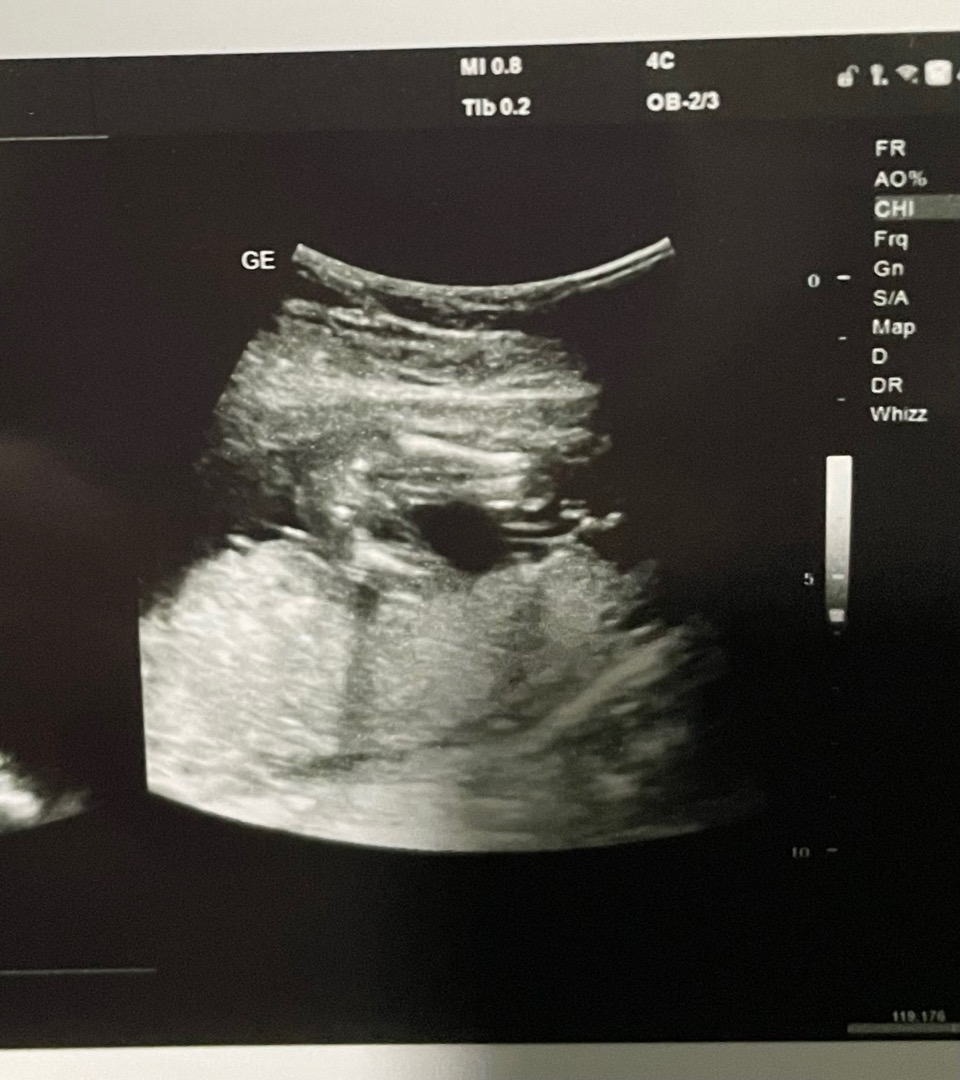

16주2일차일때 병원에서 딸일확률 90%라고 말씀해주셨는데 ㅎㅎㅎ 혹시나 다음번에 갔을때 반전이 있을까봐 조마조마 하네요 ㅠㅠ 이정도면 반전없이 확정이겠죠..????ㅎㅎ